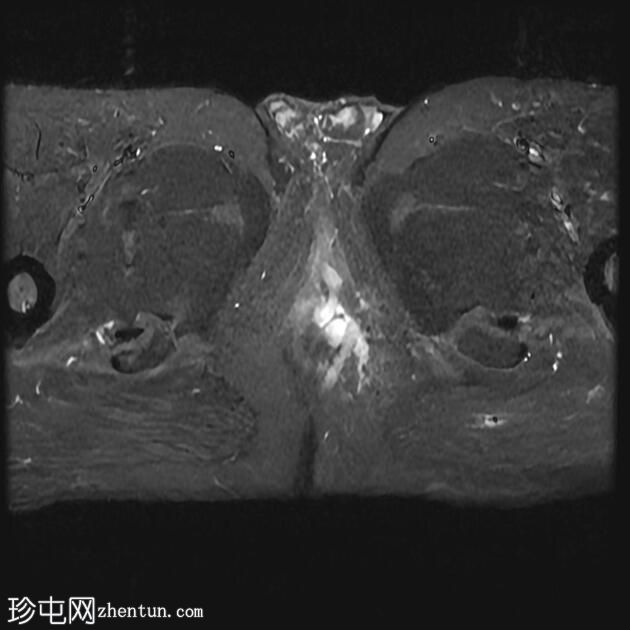

MRI

轴向位

T2

轴向位T2

脂肪饱和度

T1

轴向位T1

一条68毫米厚的强化通道始于左侧肛周区域,向上穿过肛门内外括约肌,在2点钟方向开口于肛管。

无脓肿形成。

MRI成像特征与所述左侧经括约肌肛周瘘相符。